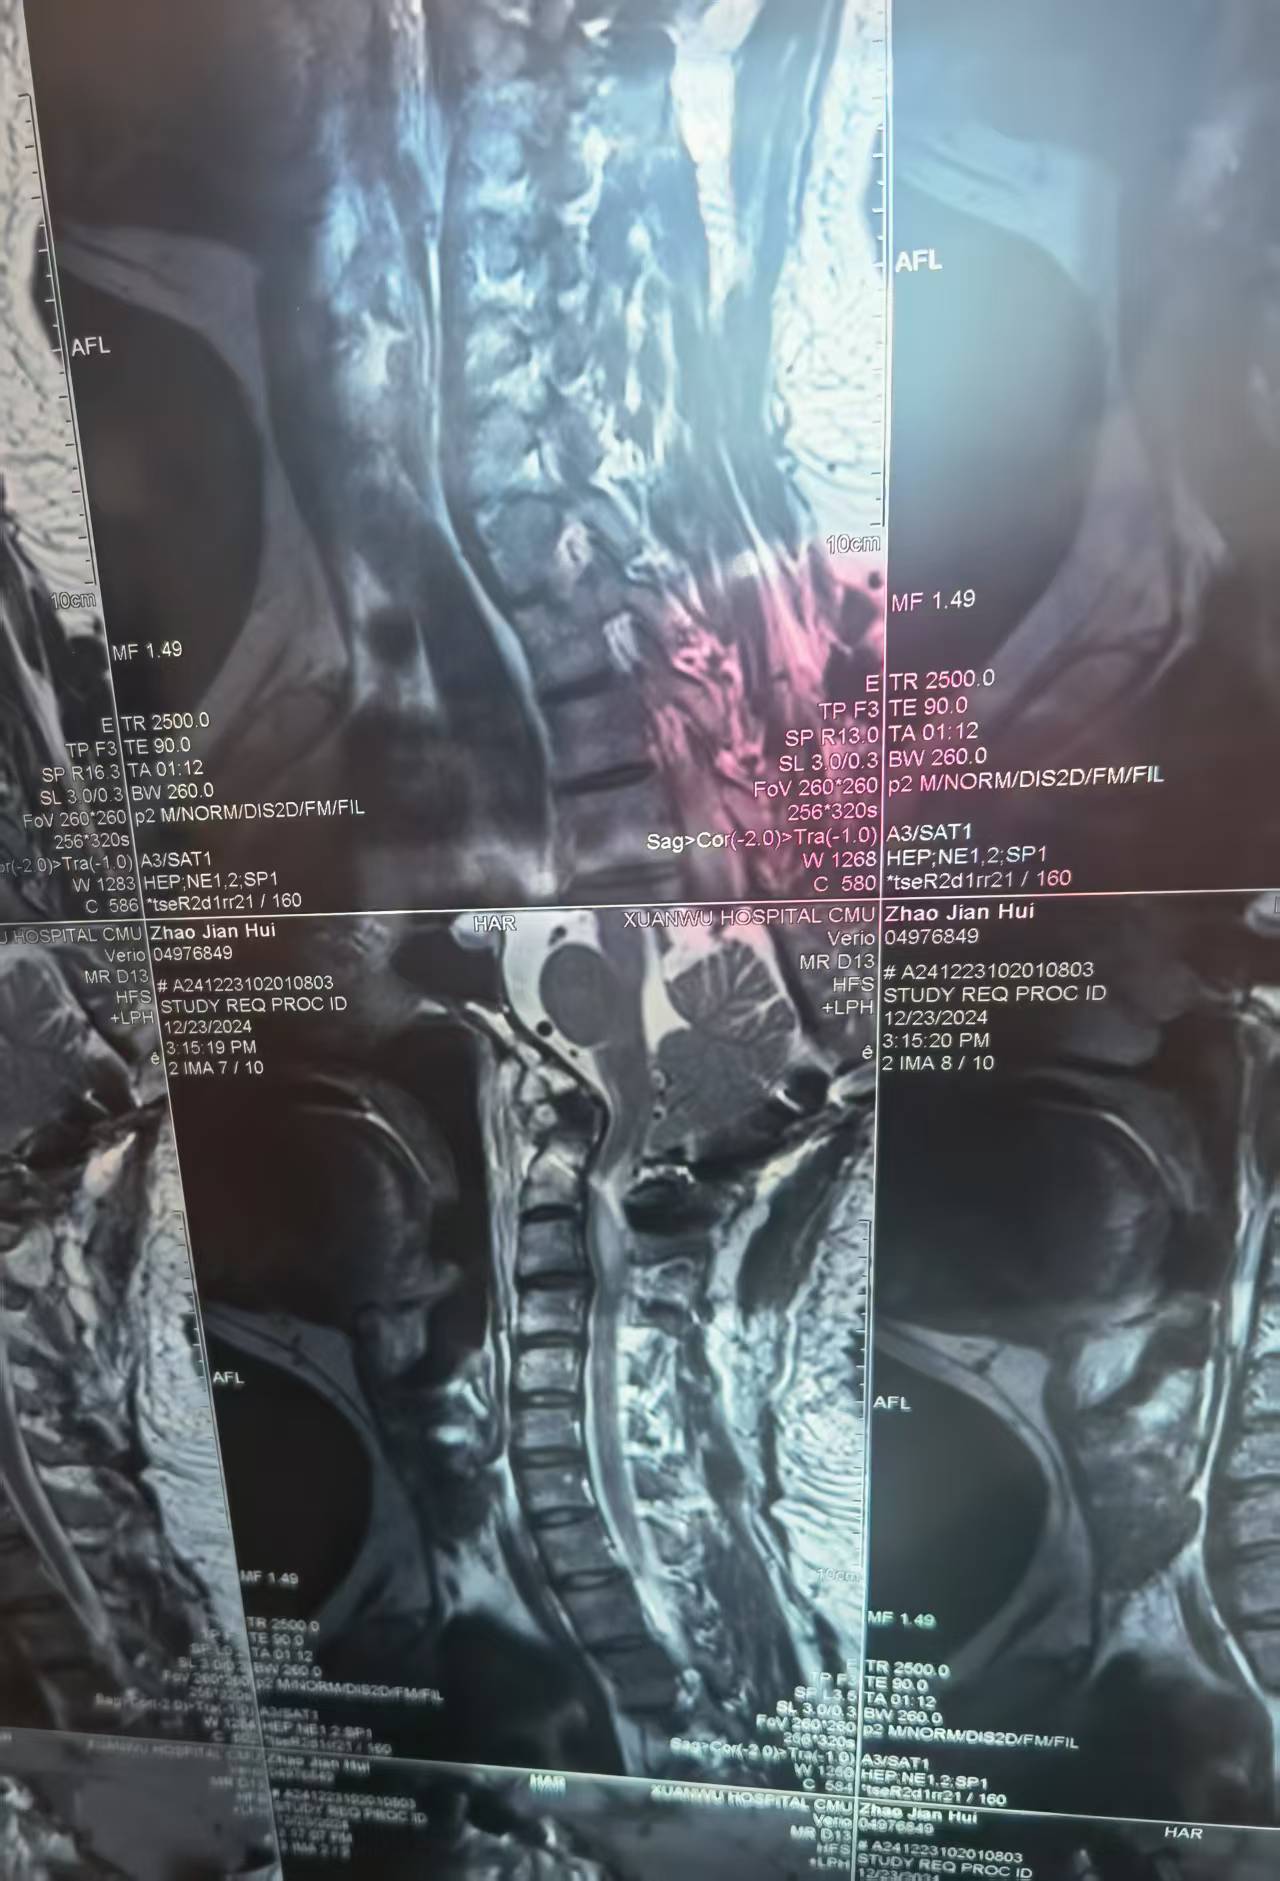

• 影像:

• 术后影像: